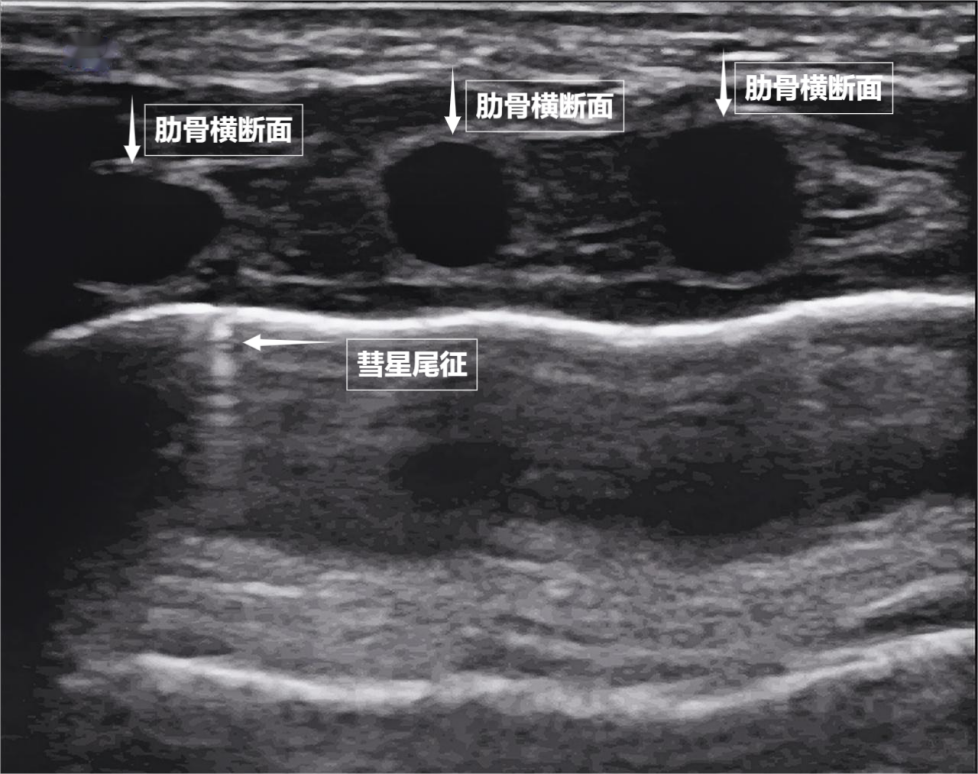

如果我们把超声图像调成实时动态模式,把“照片”变成“电影”,更神奇的一幕出现了。随着呼吸,胸膜线会随胸廓运动轻柔滑动,这就是“肺滑动征”。它意味着肺与胸壁正紧密相依、自由顺畅地呼吸。若肺与胸壁间有气胸或胸腔积液,这种滑动会消失。有时,在胸膜线下方还会出现细小的亮白色闪烁点,称为“彗星尾征”(见下图)。其少量、孤立出现时,通常是正常肺小叶间隔的反射,无需担心。

图为正常新生儿肺部超声表现